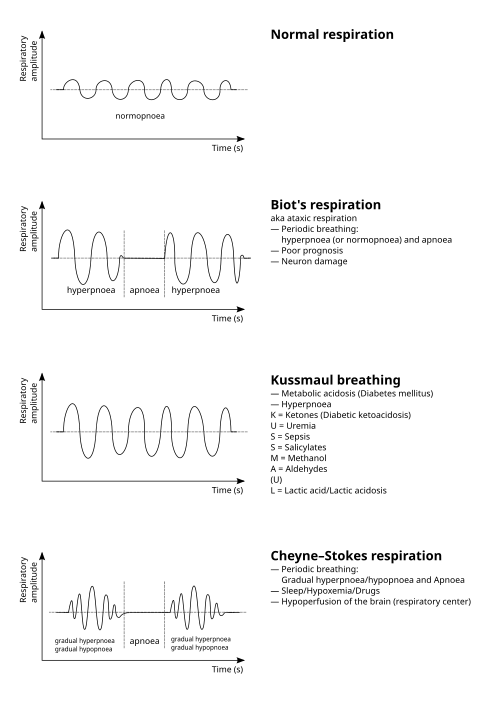

| Graph showing ataxic respirations and other pathological breathing patterns. | |

Ataxic respirations, also known as Biot's respirations or Biot's breathing, is an abnormal pattern of breathing characterized by variable tidal volume, random apneas, and no regularity.[1] It is named for Camille Biot, who characterized it in 1876.[2][3] Biot's respiration is caused by damage to the medulla oblongata and pons due to trauma, stroke, opioid use, and increased intracranial pressure due to uncal or tentorial herniation.[1][4] Often this condition is also associated with meningitis.[2] In common medical practice, Biot's respiration is often mistaken for Cheyne–Stokes respiration, part of which may have been caused by them both being described by the same person and subtle differences between the types of breathing.[1][3]

Ataxic respirations are one of many unique respiration styles in an ill patient. There is an apparent controversy surrounding the novelty of ataxic respirations versus the well-known Cheyne-Stokes and cluster respirations, which Dr. Camille Biot deemed mutually exclusive.[3] Notably, Dr. Miller Fisher was able to identify ataxic respirations in comatose patients differentiating the breathing from cluster breathing.[3]